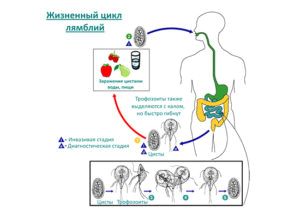

Паразити в основному розташовуються у верхній частині тонкої кишки, зустрічаються у вигляді цист або вегетативних форм.

Лямблії відносяться до класу джгутикових, представляють грушоподібної форми з вісьмома відгалуженнями у вигляді джгутиків, мають присоски, за допомогою якої вони кріпляться до стінок кишки. Цисти харчуються частинками їжі потрапила в стравохід, що дає можливість мікроорганізмам розмножуватися з великою швидкістю шляхом розподілу.

Процес розмноження такий швидкий, що вже через кілька годин кишечник людини стає покритим мільйонами лямблій. Їх стає настільки багато, що відбувається блокування стінок кишечника. Це тягне за собою порушення травлення, а також перистальтичні скорочення, що призводить до травм епітелій кишечника, мікро ерозії і вогнищ запалення.

Лямбліоз у дорослих може з'явитися різними способами зараження. Основні причини та шляхи зараження:

- погано промиті овочі фрукти,

- побутової спосіб: через заражені іграшки, посуд та постільну білизну,

- через воду, при поганій очищенню води або при купанні у відкритих водоймах,

- цисти можуть бути доставлені до людини через домашніх тварин, гризунів, а також мух.